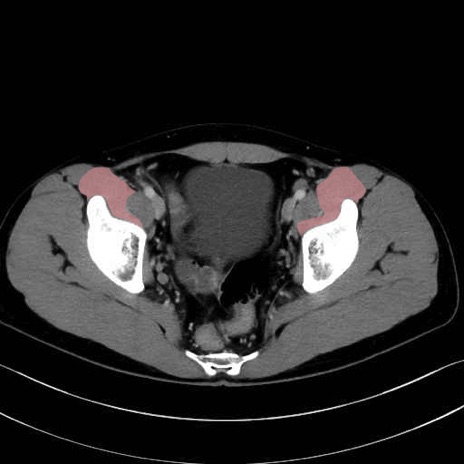

腸骨筋 (Iliacus)

肛門挙筋 (Levator ani)